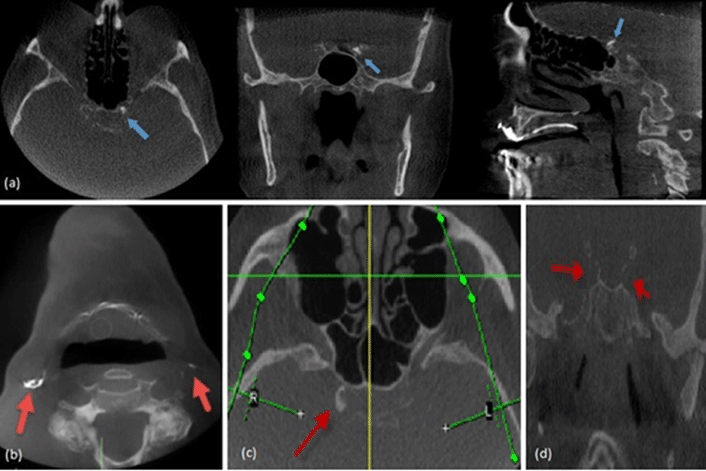

Now online in the Journal of Prosthodontics, a retrospective study analyzing the frequency of non-dental pathology in CBCT scans taken for implant placement treatment planning and post-placement evaluation.

One thousand and two CBCT scans were reviewed. A board certified oral and maxillofacial radiologist systemically read all scans. Pathologies ranged from innocuous sinusitis, to more serious atherosclerotic calcification of the carotid arteries, narrowed airways, and neoplastic lesions.

Of the 1,002 patients, 921 (91.9%) had at least one finding, underscoring the importance of proper reading and diagnosis. Fifty-one different findings were noted, of which 36 were pathologies that required referral or follow-up.